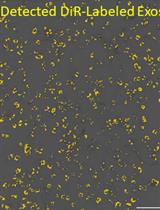

Graphical overview of extracellular vesicle (EV) isolation from plasma samples. (A) Flowchart of the isolation of extracellular vesicles from plasma, detailing plasma preparation and EV purification. (B) Transmission electron microscopy (TEM) image of EVs isolated from human plasma samples. Scale bar, 100 nm.

3. ExoView R200 platform (Software, ExoViewer 2.5.0)

4. pH meter (Thermo Scientific, model: Accumet AE150)

Procedure